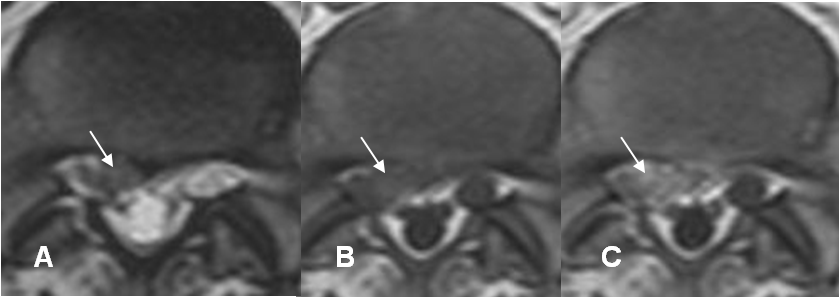

Fig 121. Laminectomía.

A: Rx AP. Ausencia de la lámina izquierda de L5.

B: RM axial en T1 y C: RM axial en T2. Cambios Post-laminectomía izquierda.